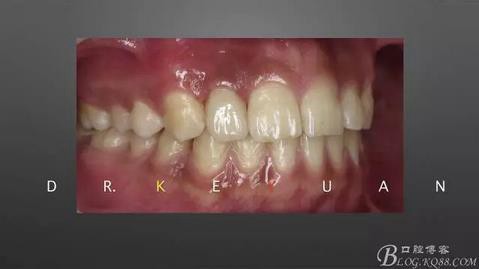

7、最終爭(zhēng)取了2周的時(shí)間,能看到牙齦有明顯的改善

360截圖20170120135245605.jpg

8、排齦、硅橡膠第二次取模制作氧化鋯全瓷冠

10、復(fù)診試戴最終修復(fù)體(又爭(zhēng)取了2周的時(shí)間,再加上技師對(duì)最終修復(fù)體鄰接關(guān)系的設(shè)計(jì),牙齦恢復(fù)效果明顯)

360截圖20170120135310260.jpg

11、牙齦狀況對(duì)比(有時(shí)候你把患者約的時(shí)間太長(zhǎng),他可能會(huì)不理解你,約著約著就再也約不過(guò)來(lái)了,有些時(shí)候患者的修復(fù)熱情和臨床的治療程序可能成反比,我們要做金玉其外、金玉其中的修復(fù),實(shí)難取舍)

360截圖20170120135321294.jpg

12、粘接后即刻(齦緣的高度略有差異,這應(yīng)該可以說(shuō)明冠延長(zhǎng)術(shù)和正畸牽引的效果差異)

13、術(shù)前術(shù)后對(duì)比